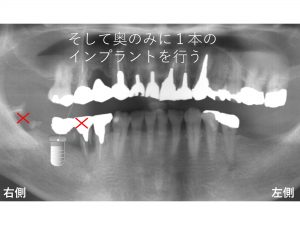

最終的には以下のようなプランとなりました。

まず奥の2歯のみ抜歯します。

手前側の歯は抜歯しないわけですから

患者様が気にしていた見た目は少しでも軽減できます。

また抜歯しないわけですからこの部分では噛めます。

そして、抜歯後に

奥のみに1本のインプラントを行います。

このインプラントが骨をくっいた後で手前の歯を抜歯します。

この歯を抜歯したと同時(同日)に仮歯を作成します。

先に手術を行なった1本のインプラントを土台にして手前の欠損部まで仮歯を延長させます。

手前の天然歯と仮歯を接着剤で固定させます。

これで抜歯と同時に噛むことが可能になり、

見た目の問題も解決されます。

以下は先日のインプラント手術直後です。

現在この歯は割れているが患者の希望もあり暫くはこのまま経過をみる予定です。

予定では数ヶ月後に予定通り、抜歯し、仮歯を作成します。